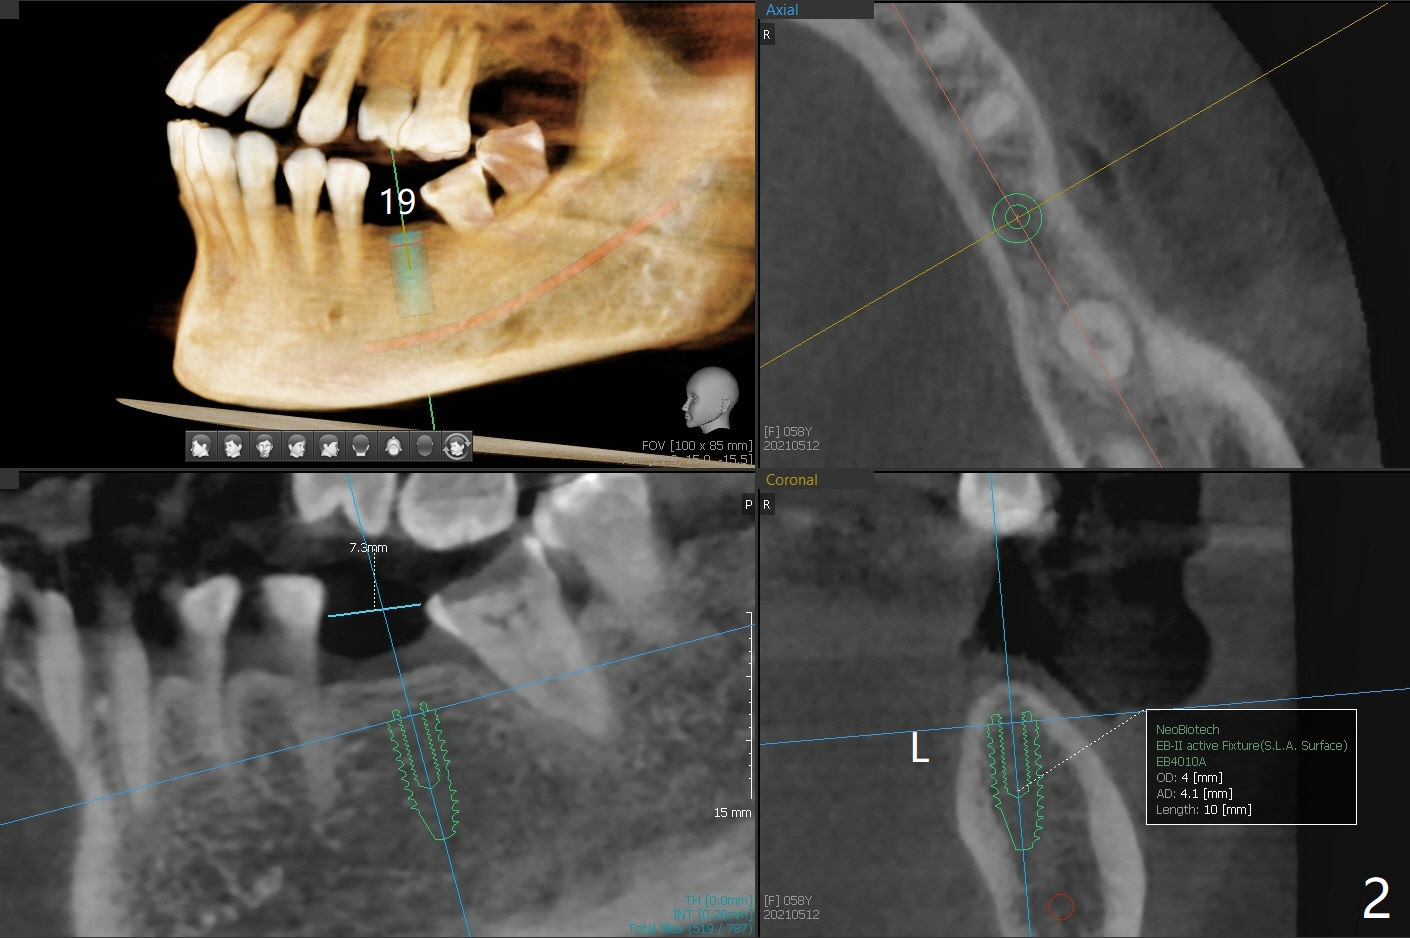

A 58-year-old woman with several restoration agrees to have implants at #15 and 19 (Fig.1). Since #18 tilts mesially, which needs to be trimmed, place #19 implant slightly distal, ~ .5 mm (Fig.2). As the infection at #14 is extensive (Fig.3), place #15 implant (probably 5x7.3 mm) distal, while tilts the long axis of the implant mesially (Fig.4 arrow). Also move the implant palatal with larger diameter and shortened length. Forget about the implant #15 if it is difficult or impossible to change.